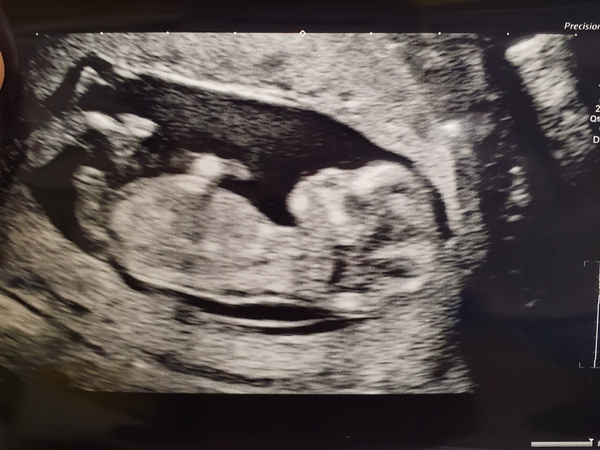

Had a scan today as been bleeding again, our little wriggler is measuring ahead at 12+2 but will find out officially at dating scan next week. They said the bleeding could be placenta moving, has anyone had this before?

@sao81 Not had any bleeding myself and this is my first, but have seen plenty of Mums on the forum who've had bleeds and everything is perfectly fine, sending loves as it must be worrying. Love the pic of your little wriggler _ xxx

@sao81 Lovely scan pic, glad everything is ok!

Had my scan today and they have put me forward by 3 days. Now waiting nervously on the blood results for the screening. I am sure he said it was a 1.06 when he measured it but means nothing to me